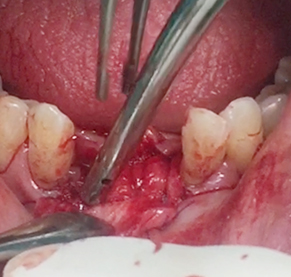

Simultaneous bone graft and implant placement